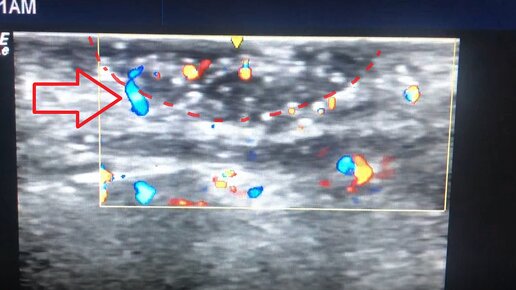

Определение толщины базалиомы с помощью кожного УЗИ-датчика для выбора оптимального метода лечения